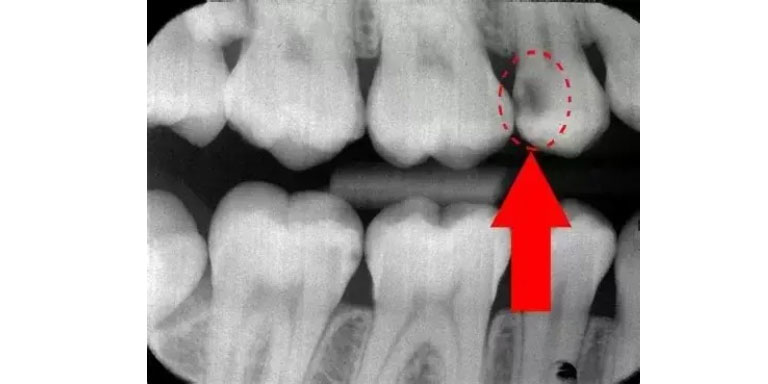

Digital X-ray & Diagnosis

We identify the infection and assess your tooth’s health.